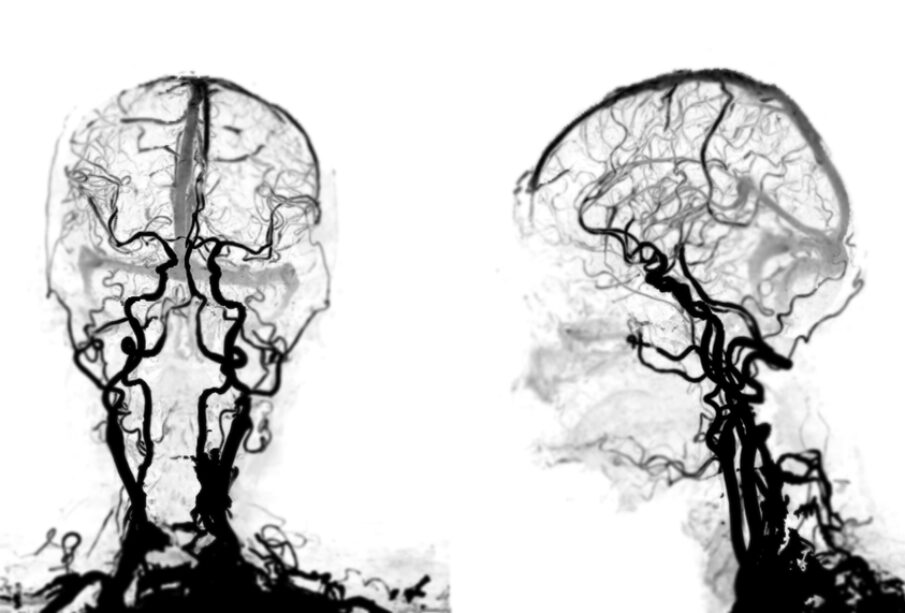

Pavyzdžiui, susiaurėjusios vainikinės arterijos gali sukelti krūtinės anginą, širdies ritmo sutrikimus ar dusulį. Jei užsikemša miego arterijos, gali pasireikšti insultui būdingi simptomai: staigi silpnumo banga, kalbos arba regos sutrikimai, galvos svaigimas, stiprus galvos skausmas arba sąmonės praradimas.